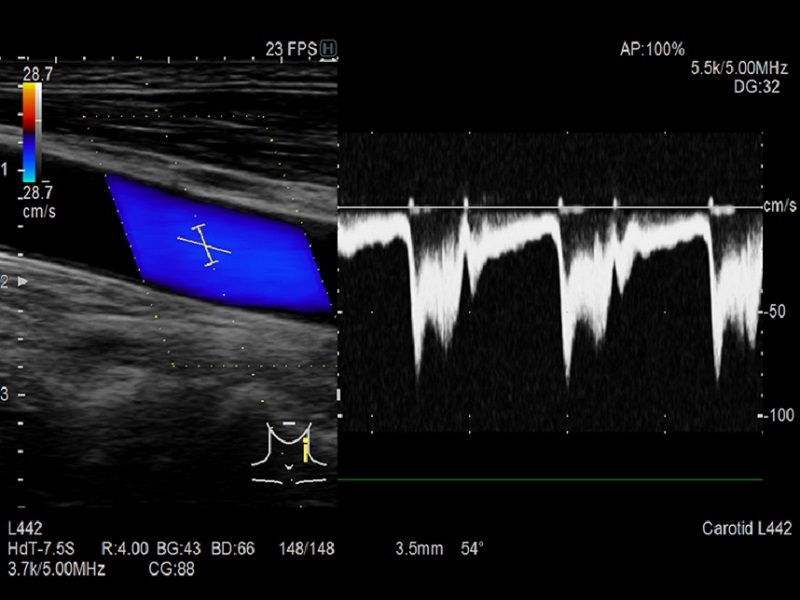

Dual Gate Doppler

- Collects Doppler waveforms from two locations during the same heart beat

- Enables faster and more accurate measurement of LV diastolic performance indicators

- Useful in diagnosis of fetal arrhythmia and Carotid stenosis

Dormed Hellas AR65 – Vascula Carotid Dop Dormed Hellas AR65 – Vascular Carotid Dual CF